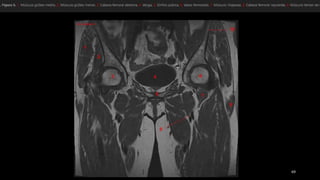

• Glúteo mayor (GMa)

• Glúteo medio (GMe)

• Glúteo menor (GMi)

• Fascia lata (FL)

• Tendón del glúteo menor (1)

• Aanterior del tendón del glúteo

medio (2)

• Posterior del tendón del glúteo

medio (3)

• TM, trocánter mayor

• Tm, trocánter menor.

• Glúteo mayor(GMa) • Glúteo medio (GMe) • Glúteo menor (GMi) • Fascia lata (FL) • Tendón del glúteo menor (1) • Aanterior del tendón del glúteo medio (2) • Posterior del tendón del glúteo medio (3) • TM, trocánter mayor • Tm, trocánter menor.

• #65 Características anatómicas de los músculos y tendones de la región externa (abductores) de la cadera. Dibujos de una vista coronal de la cadera obtenida de anterior (a) a posterior (e) que ilustra las relaciones entre los músculos glúteo mayor (GMa) , glúteo medio (GMe) y glúteo menor (GMi), la fascia lata (FL), el tendón del glúteo menor (1), la porción anterior del tendón del glúteo medio (2) y la porción posterior del tendón del glúteo medio (3). El glúteo menor es el más pequeño, profundo y anterior de estos músculos. El glúteo medio se localiza lateral y posterior al glúteo menor. El glúteo mayor es el más grande, superficial y posterior de dichos músculos. Con relación a estos músculos, la fascia lata es la estructura más superficial. TM, tro cánter mayor; Tm, trocánter menor.